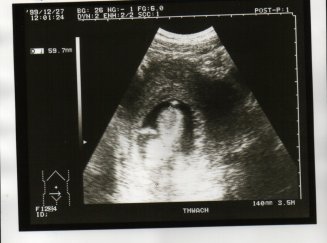

(附圖:製造業產品生產過程存證。小學生可能為天使族裔,由此照片即可看出一二 ^_^。時小學生年方13週又3天,in his mom)